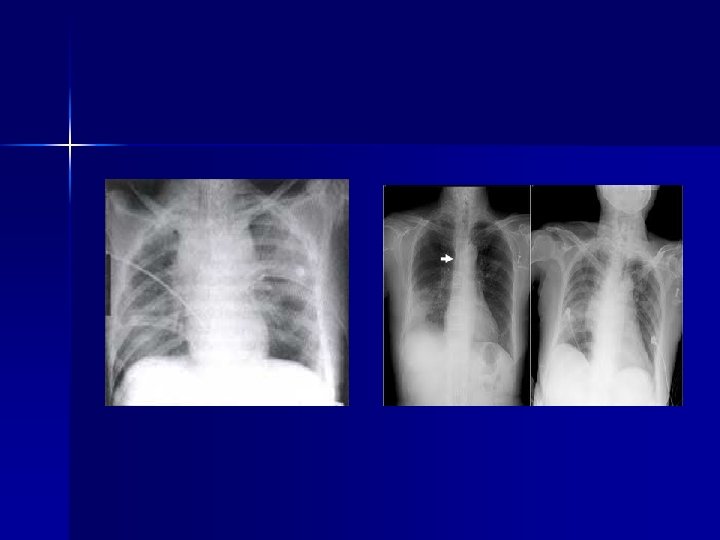

TÓRAX n Trauma cerrado o contuso x desaceleración: -Transección de Aorta -Rx con ensanchamiento mediastinal -> 8 cms (AP) -Desplazamiento de la tráquea -Depresión del bronquio izquierdo -Desviación de la SNG, etc

TÓRAX Se relaciona con lesiones imp de Aorta: -Fx esternón -Fx 1 era y 2 da costillas -Fx de escápula n Si hay sospecha de lesión de Aorta: -Aortografía -TAC -ECO transesofágico n